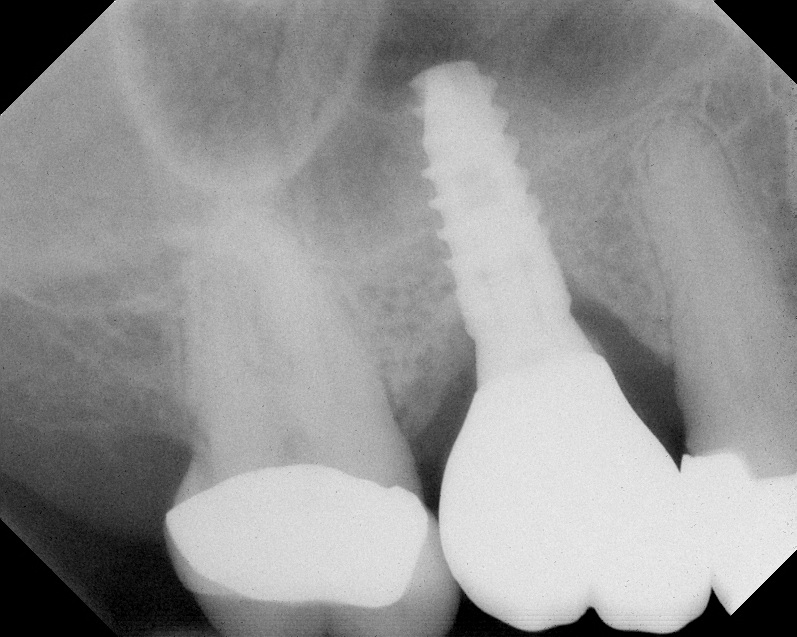

Radiograph of implant N o. 3 and sinus augmentation, day of placement. There is about 2 mm to 3 mm of native bone, and the sinus has been raised about 8 mm to 9 mm.

Fig. 10

A 7-month postoperative radiograph of the restored implant No. 3.

Fig. 11